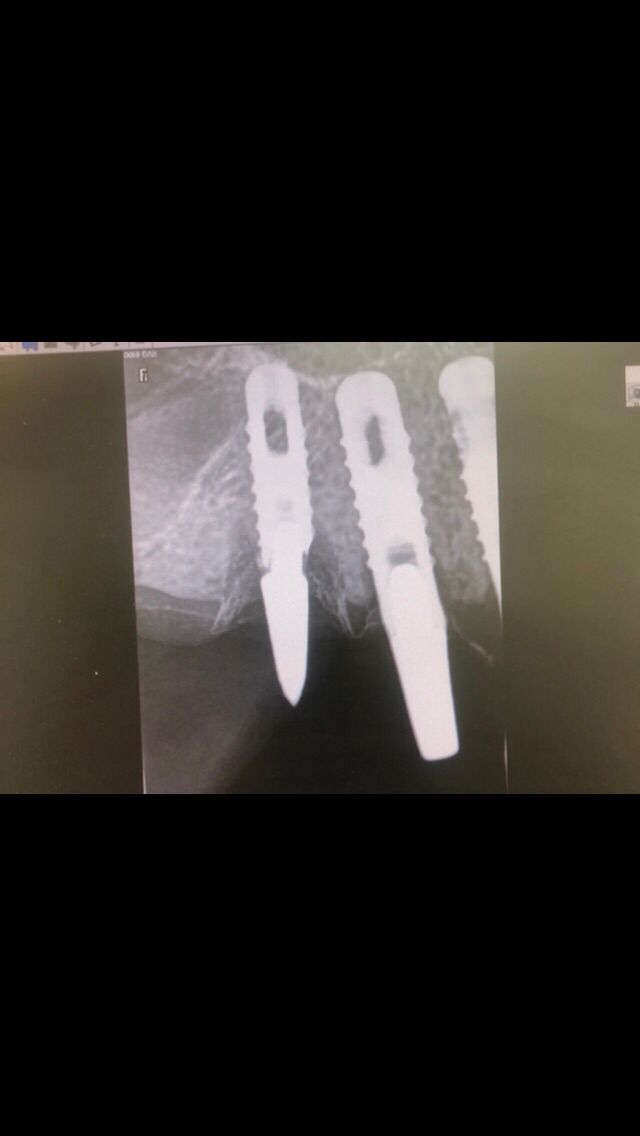

Actualmente vuelve el paciente de nuevo con la misma prótesis. Había roto dos de los tres pilares en concreto los más distales. El primero de los dos había roto la rosca del aditamento dentro del implante como ocurre habitualmente. Pero el ultimo pilar había roto directamente la cabeza del implante tal como se ve en la radiografía y lo que quedaba era un cilindro de titanio macizo perfectamente integrado en el maxilar, sin posibilidad de enroscar nada. Le explicamos al paciente que habría que quitar y poner un implante en el mismo acto. El paciente dijo que no, así que decimos que no se haría cirugía. Buscamos solución alternativa: hacemos un un agujero en el centro del macizo cilíndrico del implante roto y pasamos sucesivamente el set de machos roscantes. Utilizamos una fresa cañón de 1 mm que poco a poco se va introduciendo hasta 8mm con un poco de vagación, que hace que sea un poco mas de 1mm de diámetro. Posteriormente pasamos el conjunto de machos roscantes de métrica 2mm para poder usar un aditamento experimental, que era un palo de rosca de diámetro 2 mm unido a un cuerpo metálico en forma de sombrero napoleónico fabricado en cromo/cobalto, prototipos primitivos de la sistemática ASATIM y que tienen la característica de tener gran resistencia a la fractura. Nos llevó un tiempo largo el tallado de dichos aditamentos, tal como se puede observar en las imágenes, y tras cicatrizar la encía se le hizo una prótesis estándar. Esperemos que no lo rompa más veces.